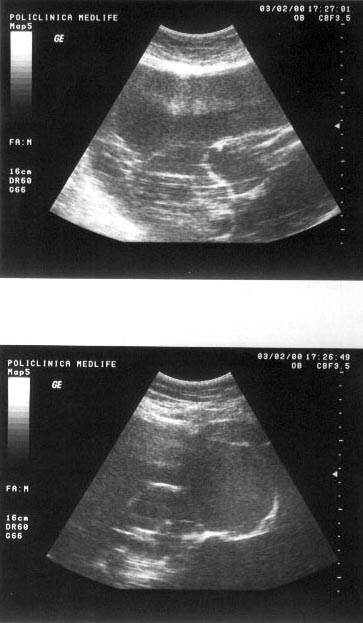

Figura

14. Mas[ gigant[ care ocup[ micul bazin =i abdomenul mediu, de aproximativ

30 cm diametru, cu structur[ complex[ 80% lichidian[, restul solid[. Partea

solid[ este dispus[ sub form[ de septuri. Aspectul sugereaz[ histademom cu

apartenen[ ovarian[.